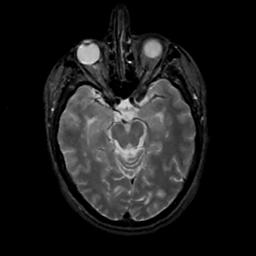

MR Study #8, March 31, 1991 -- Slice #19

[Home][Help][Clinical][Tour 1][Tour 2] Slice 19